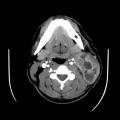

Tomodensitométrie cervicale

TUBERCULOSE